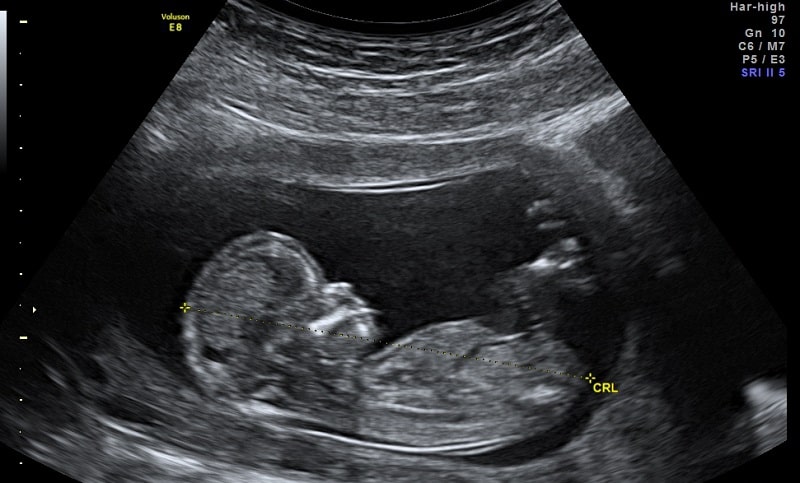

La revue scientifique Nature Communications a récemment publié une étude clinique marocaine sur l’automatisation de la biométrie fœtale et les évaluations du volume de liquide amniotique. Elle vient de valider scientifiquement la solution élaborée par la start-up DeepEcho.

Selon cette étude, la biométrie fœtale et les évaluations du volume de liquide amniotique sont deux tâches essentielles mais répétitives dans les échographies de dépistage fœtale, aidant à la détection d’affections potentiellement mortelles.

Selon la même source, ces deux tâches sont essentielles dans l’écographie fœtale "parce qu’elles permettent de détecter le retard de croissance intra-utérin, première cause de mortalité fœtale dans le monde, et les anomalies liées à la quantité du liquide amniotique, dont nous avons automatisé la quantification", explique-t-il.

L’intérêt de cette étude relève de son caractère prospectif. Ces modèles automatisés ont été formés à l’aide d’une base de données récentes constituées de 172.293 images échographiques fœtales marocaines anonymisées.

"Nous avons développé des modèles à partir de données récoltées et les avons testés dans ces quatre centres, dans le cadre de cette étude, qui a concerné 172 patientes. Le but était de comparer nos mesures à celles d’un médecin expert", précise Saad Slimani. Son équipe, marocaine, composée d’une dizaine de médecins, de quatre ingénieurs et de douze médecins annotateurs, a constaté que ces mesures concordaient avec celles d’un spécialiste, et qu’elles sont donc précises et fiables.